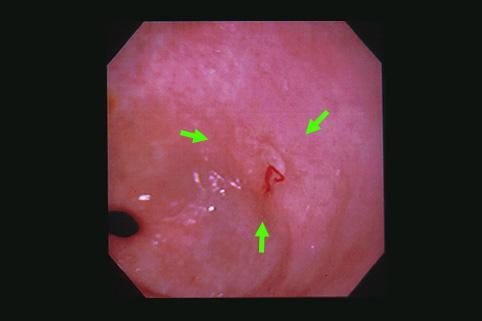

clasificación del pacienteTumor Epitelial Maligno/Adenocarcinoma

parte(separada por órganos)estómago(región)/antro

método de exámenEndoscopia

clasificación ectoscópica de tumoresTipo 0(tipo superficial)/Tipo IIc(IIc)

diámetro mayor del tumor1 - 9

grado de penetraciónm